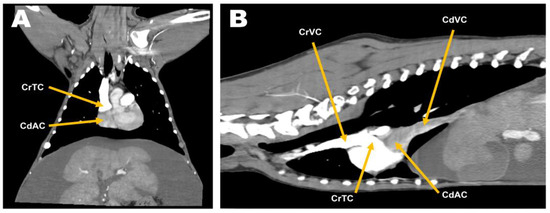

Four days after the procedure, the patient showed normal demeanor and appetite, with no residual ascites (Figure 5A,B). On echocardiography, on day 6 after surgery, normal right atrial flow was detected with no residual obstruction between the cranial and caudal right atrial chambers (Figure 5C,D). There were no specific complications, such as re-stenosis or recurrence of clinical signs related to CTD at the 1-year postoperative follow-up.

Figure 5. Comparison of preoperative and postoperative diagnostic imaging. Severe abdominal distention and decreased serosa detail (A) improved at postoperative day 4 (B). The remnant membrane ((C), orange arrow) obstructing venous blood inflow from the caudal vena cava was successfully excised (D), and blood inflow was not disturbed.